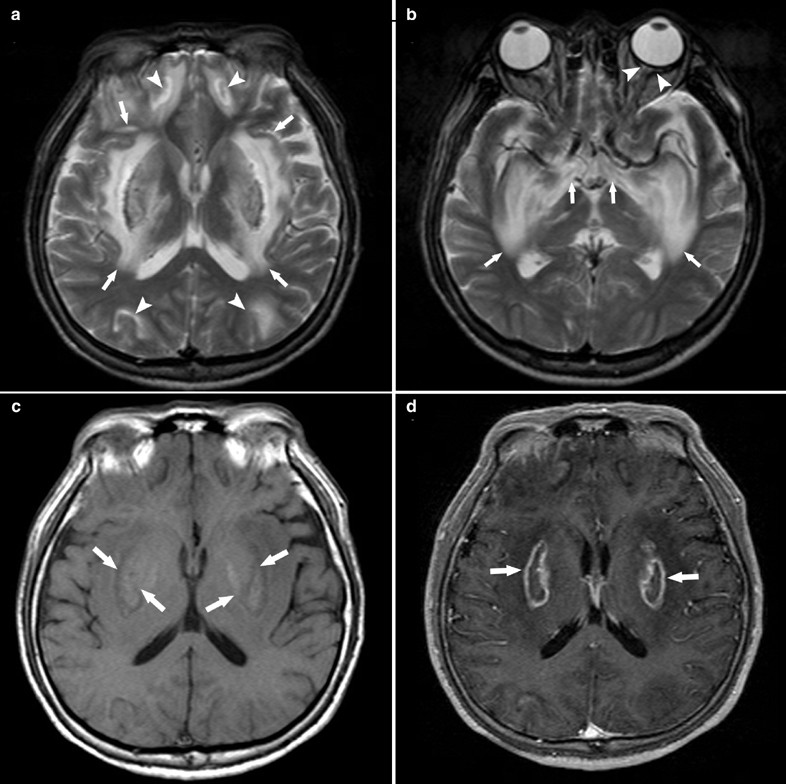

Ocular Manifestations And Mri Findings In A Case Of Methanol Poisoning Eye